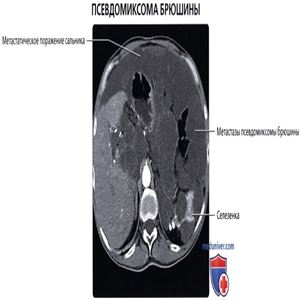

КТ с контрастированием, аксиальный срез: классическая картина псевдомиксомы брюшины: метастатическое поражение брюшины муцин-продуцирующей опухолью червеобразного отростка приводит к формированию скопления желатинообразного вещества в брюшинной полости. Формирование капсул и количество вещества обусловливают характерный масс-эффект, или вдавления, на внутренние органы полости живота и часто вызывают обструкцию кишечника.

КТ с контрастированием, аксиальный срез: у этого же пациента определяется сложный (с наличием перегородок) характер «асцитической жидкости», часто являющейся полужидким желатинообразным веществом. Метастазы наблюдаются по всей полости брюшины, включая метастазы, расположенные по поверхности печени, сальника и боковых каналов брюшной полости. Обратите внимание, что почки не подвержены влиянию опухоли благодаря своему забрюшинному положению.